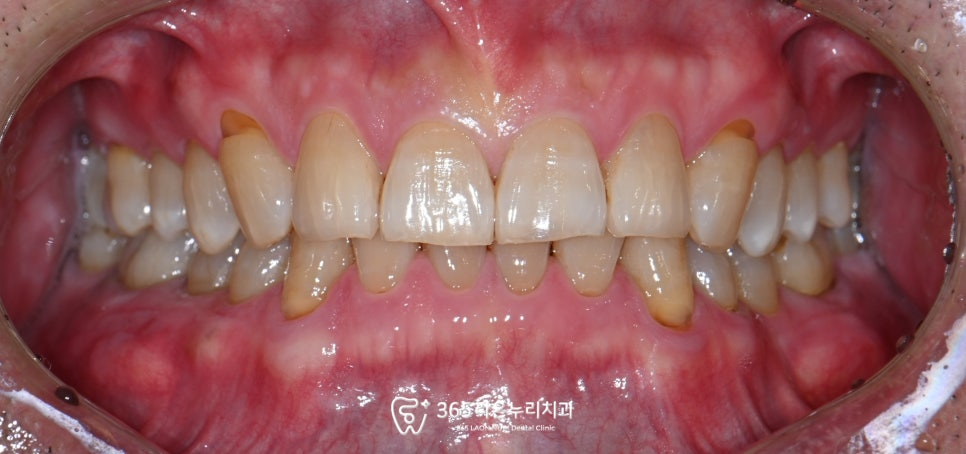

정면에서 찍은 사진을 보면

치경부 마모증이 보이지만

큰 문제가 보이지는 않았습니다.